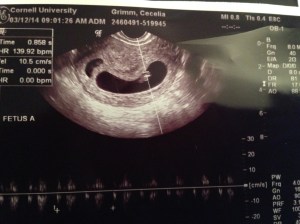

Well Baby G a lot has happened since our last blog, and perhaps the biggest news is that you are a GIRL! Mommy and Daddy found out yesterday that we have a little princess on the way 🙂 Mommy and your Nana and Aunts were all convinced that you were a boy, but you’re Daddy kept saying all along that you were a little girl…sure enough he was right. We are so excited and the doctor said you are healthy and look great. Now that we know you are a girl we can begin planning your nursery and narrowing down name choices. I’m going to call it now based on your behavior during the doctor’s appointment – you are going to stubborn just like your Mommy. You did not want to cooperate during the ultrasound, every time the nurse tried to get you to move you would roll the other way. You were scrunched up in a ball with your hands and feet in your face. You are very flexible and I think you are going to have long fingers just like Mommy.

At this point we are at Week #21 and you are the size of a pomegranate. Continue to stay strong and healthy Princess G! We love you xoxoxoxoxoxoxo

Almost at the ninth week and I feel good for the most part – a little tired and have nausea all day, but other than that I feel fine 🙂 We “graduated” from Cornell at the seventh week and now on to my OBGYN. My next appointment isn’t until April 2, 2014 – seems so far away – and makes me a little nervous. What some don’t realize is that when you undergo infertility treatment you get so used to going to the doctor 3-4 times a week for constant monitoring, that waiting a few weeks until your next appointment can feel strange and is nerve wrecking. I’m sure all is fine and I tell myself that the daily nausea is a positive sign that the pregnancy is going as it should be 🙂 I celebrated my 35th birthday last week with you, and I can’t think of a better gift than being pregnant. This year is going to be great and I look forward to every moment until October 26, 2014 – our due date! In the meantime, I will continue talking to my belly and sending words of love and encouragement. I pray every day that you get stronger and bigger. At this point, you are the size of a raspberry – and next week the size of a green olive. I love you Baby Grimm xoxoxoxoxoxoxoxo